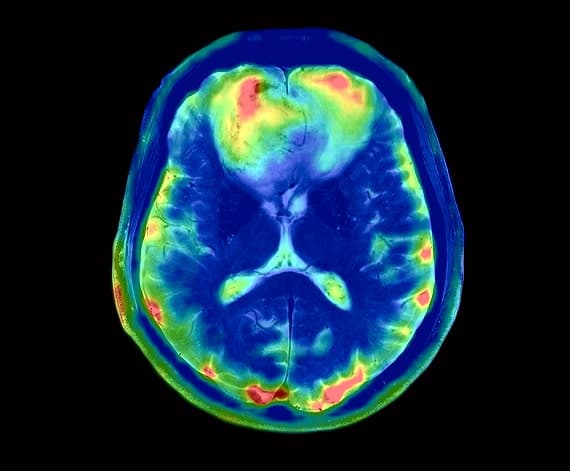

NeuroQuant®

Automated Brain Volume Analysis. NeuroQuant® provides FDA-cleared, objective measurements of brain structures. By quantifying volume changes, we help clinicians detect and track early-stage atrophy associated with Alzheimer’s, dementia, and epilepsy.